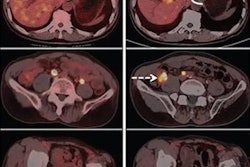

Volunteer patients underwent one whole-body Ga-68 FAPI-46 PET/CT scan (Biograph 64 mCT or Biograph 64 TruePoint, Siemens Healthineers) and subsequently, surgical resection of their primary or metastatic tumor. Lastly, the researchers compared Ga-68 FAPI-46 PET maximum standardized uptake values (SUVmax and SUVmean) with FAP immunohistochemistry scores in cancer and noncancer tissues for each patient.

Image courtesy of the Journal of Nuclear Medicine.They found Ga-68 FAPI-46 SUVs and immunohistochemistry scores were higher in cancer than in normal tissue: mean SUVmax 7.7 vs. 1.6 (p < 0.001), mean SUVmean 6.2 vs. 1.0 (p < 0.001) and mean FAP immunohistochemistry score 2.8 vs. 0.9 (p < 0.001). In addition, FAP immunohistochemistry scores strongly correlated with Ga-68 FAPI-46 SUVmax (r = 0.781) and SUVmean (r = 0.783) across all cancer types.